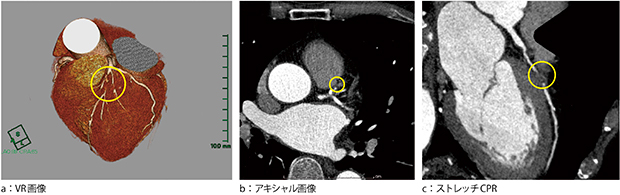

冠動脈CTA

図3は,循環器科オーダの冠動脈CTの画像である。CTA#6に高度狭窄または完全閉塞を認める。VR画像,CPR画像で良好な描出が得られている。

図3 冠動脈CTA

#6に高度狭窄または完全閉塞を認める。